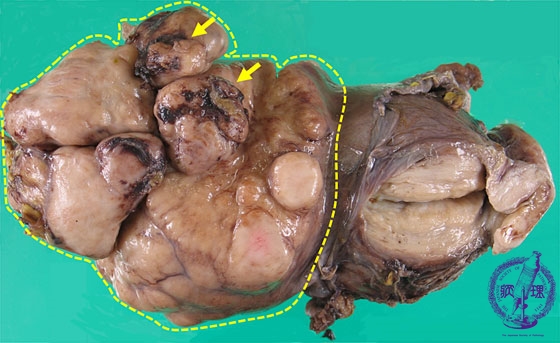

- ★(3)leiomyosarcoma

Macroscopic appearance: A milky white colored and solid tumor (yellow dotted line) with partial hemorrhage and necrosis (yellow arrow).